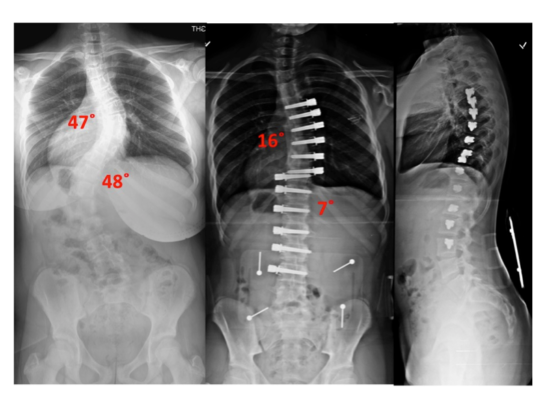

Does Scoliosis Surgery Make You Taller: Understanding the Effects of Scoliosis Surgery on Body Height and Alignment

Spinal Fusion for Scoliosis: Long-Term Effects: How Spinal Fusion Impacts Quality of Life and Functionality